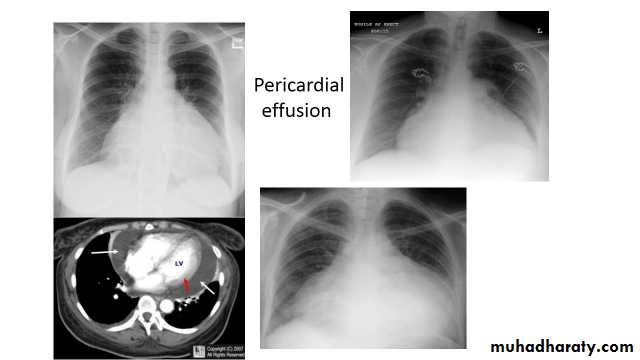

Pericardial effusions occur when fluid collects in the pericardial space (a normal pericardial sac contains approximately 30-50 mL of fluid).

Radiographic features

Plain radiograph

a very small pericardial effusion can be occult on plain film there can be globular enlargement of the cardiac shadow giving a water bottle configuration known as Globe shape heart or pumpkin shape heart

.